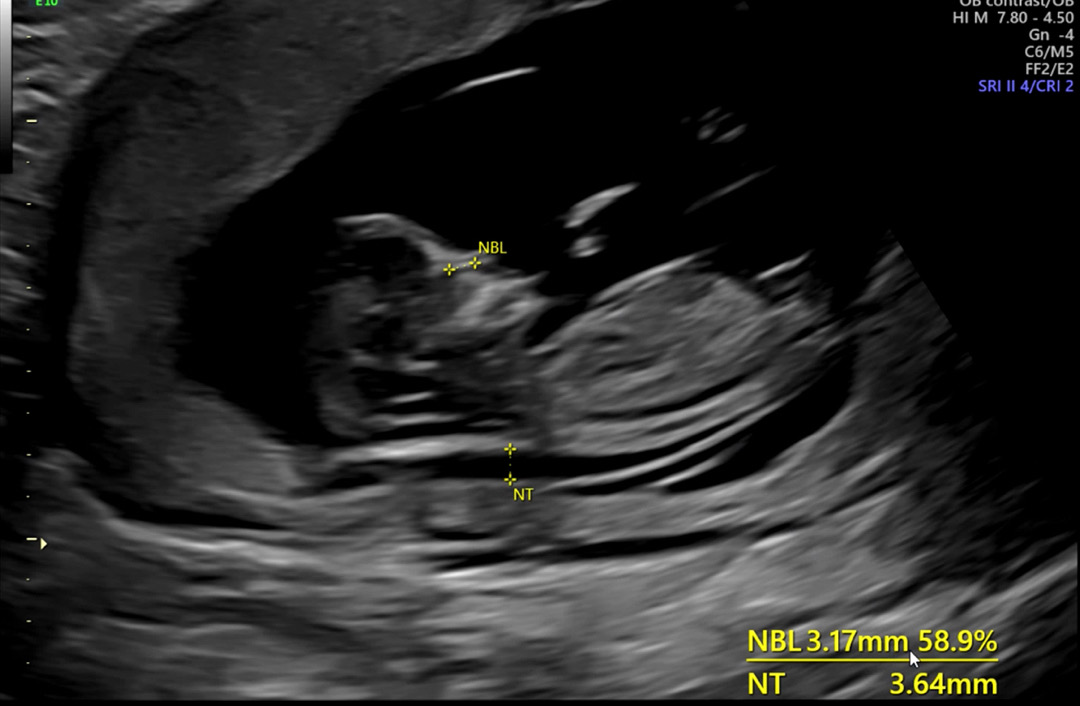

기다리고 기다리던 1차 기형아검사 하구왔어요...! 나머지는 다 정상이라는데.. 목덜미 투명대가 애매하게 두껍다네요 ㅠㅠ 4번 해본결과 2번은 3mm이상 2번운 2.9mm정도... 3주후에 양수검사 하자네요 별 이상 없겠죠 ㅠㅠ 양수검사 해보신분들 있으실까요 채혈도 매번 무서워하는데...검사 얘기 듣자마자 걱정+두려움+무서움으로 펑펑 울고왔어요 별 이상 없길 •••!

12주4일에 했어요 ㅜㅜ